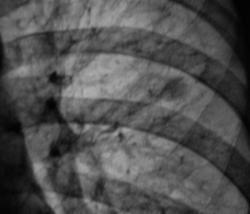

102._Rasshifrovka..jpg

А плотные включения все таки есть.

Могу ошибаться, но сдесь включения есть.

Всмысле на 27 снимке.

А на боковой рентгенограмме, вроде-бы кропноочаговая тень не одна? А вроде-бы две?